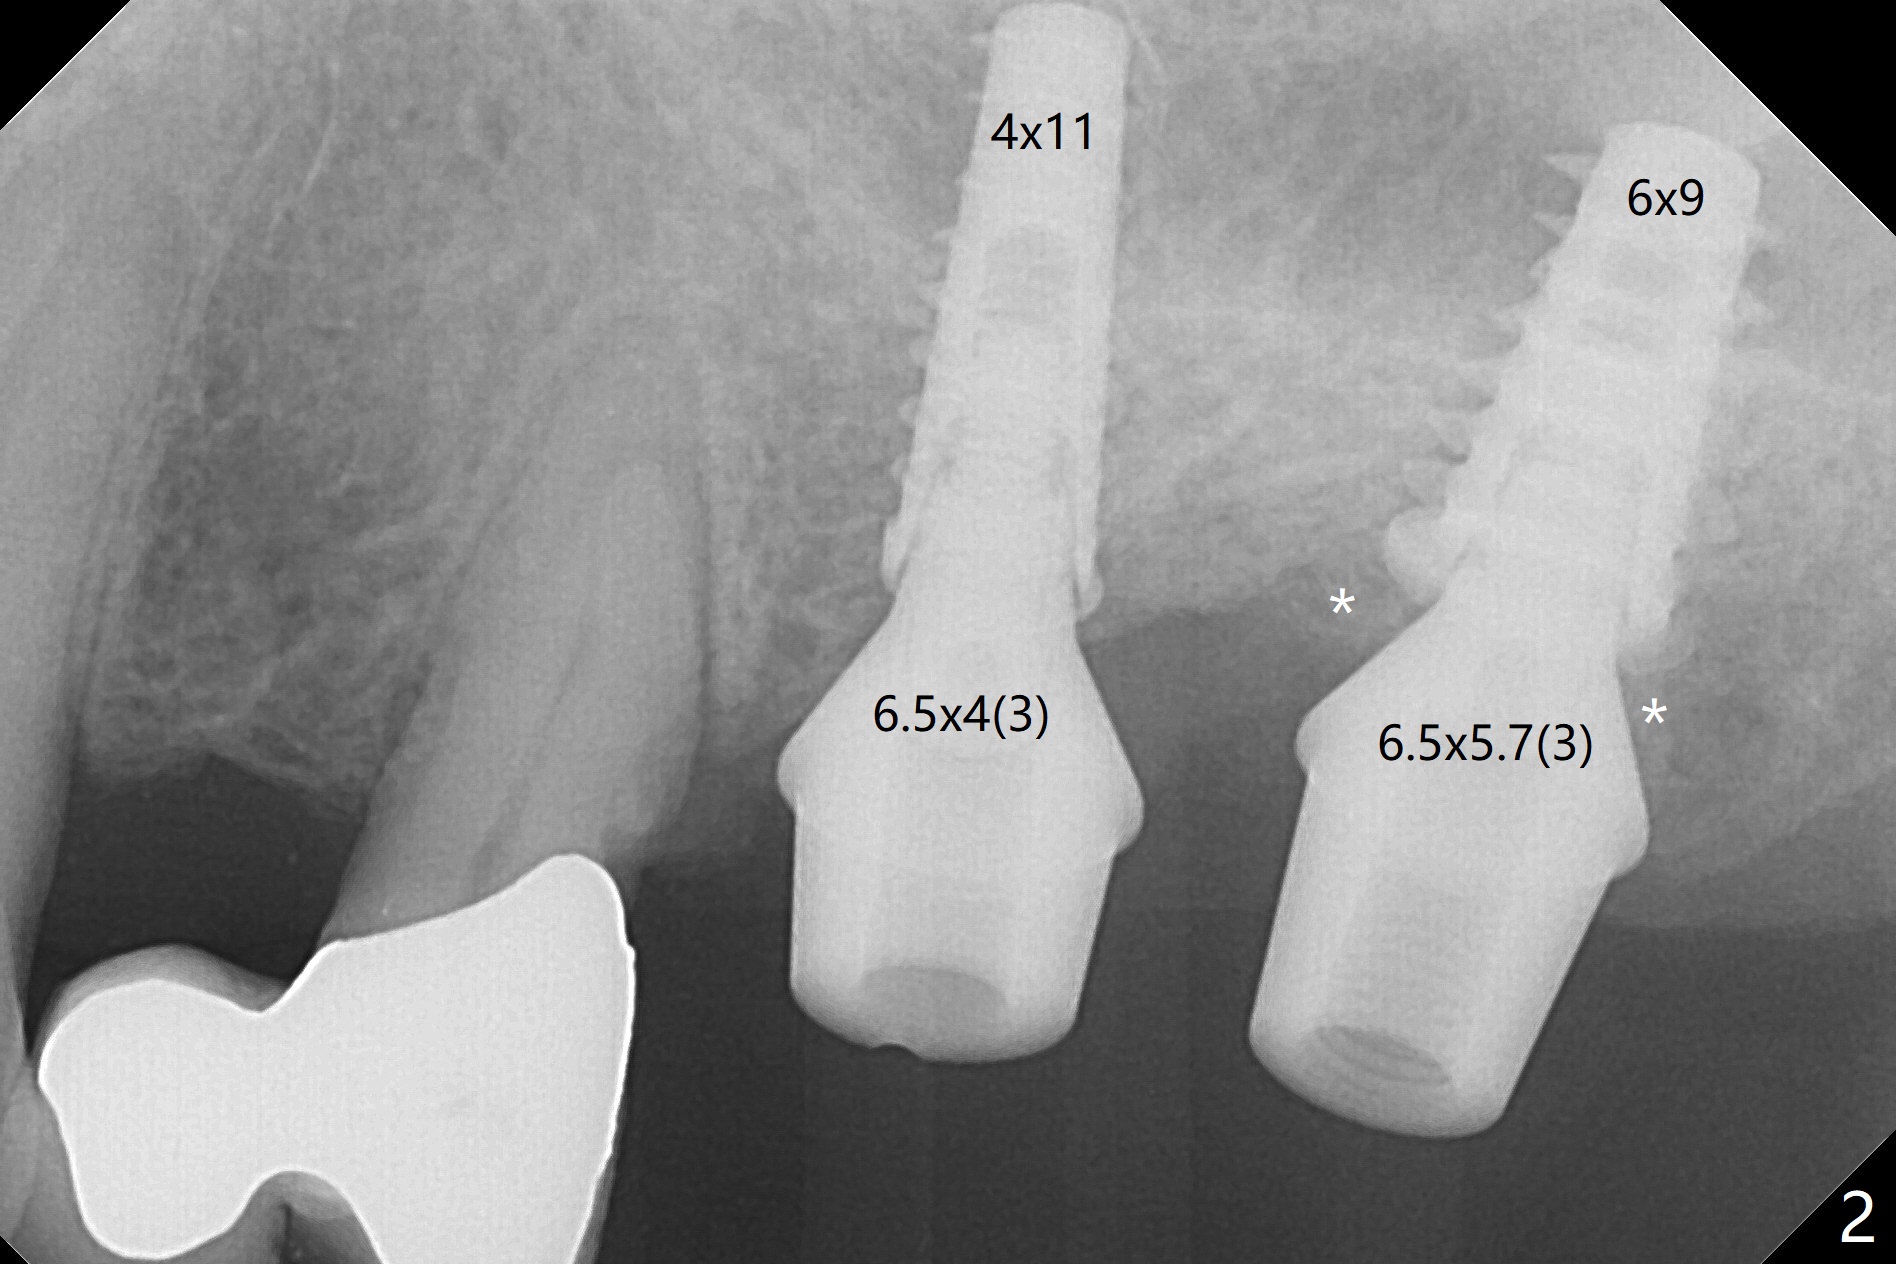

Due to irregular shape of freshly extracted socket at #15, control of depth is difficult. The sinus membrane is perforated after use of bone spreader, probably associated with drills longer than expected. SM taps (5.0 and 5.3 mm) do not achieve stability. When a 5.5x9 mm IBS dummy implant is inserted, initial stability is obtained (Fig.1). Osteotomy at the edentulous area of #14 is uneventful with insertion of a 4x11 mm dummy implant (without involving the sinus floor apparently clinically as well, Fig.1). After adjustment of trajectory, a 4x11 mm definitive implant is placed at #14 with ~ 35 Ncm, while a 6x9 mm implant is placed at #15 with ~35 Ncm (Fig.2 (*: Vanilla Graft with Osteogen)). Periodontal dressing is applied around the abutments and neighboring teeth. There is mild oral and nasal hemorrhage postop. In fact the patient has history of stroke with oral Plavix intake. The medicine stops 4 days preop and is advised to resume after hemostasis is achieved. The patient returns 3 months postop (Fig.3). After changing abutments to 5.5x5.7(3) mm, impression is taken. The crown/abutment at #14 is loose 1 year 10 months post cementation. After use of 5.5 mm profile drill, the crown/abutment is reseated, but the seating is incomplete (Fig.4 <) because of contact of the abutment with the mesial crest (*). A larger profile drill does not help (Fig.5). When a narrower abutment (4.5x7.5(3) mm) is torqued, it appears to be completely seated (Fig.6). After distal surface adjustment of the abutment, impression is re-taken. There are 3 other unfavorable conditions: poor crown/implant ratio and trajectory and #18 missing. The abutment at #14 must have been prepared for parallelism before impression. Return to Upper Molar Immediate Implant, Prevent Molar Periimplantitis (Protocols, Table), Armaments No Deviation Prevent Screw Loosening Xin Wei, DDS, PhD, MS 1st edition 11/28/2017, last revision 02/23/2021